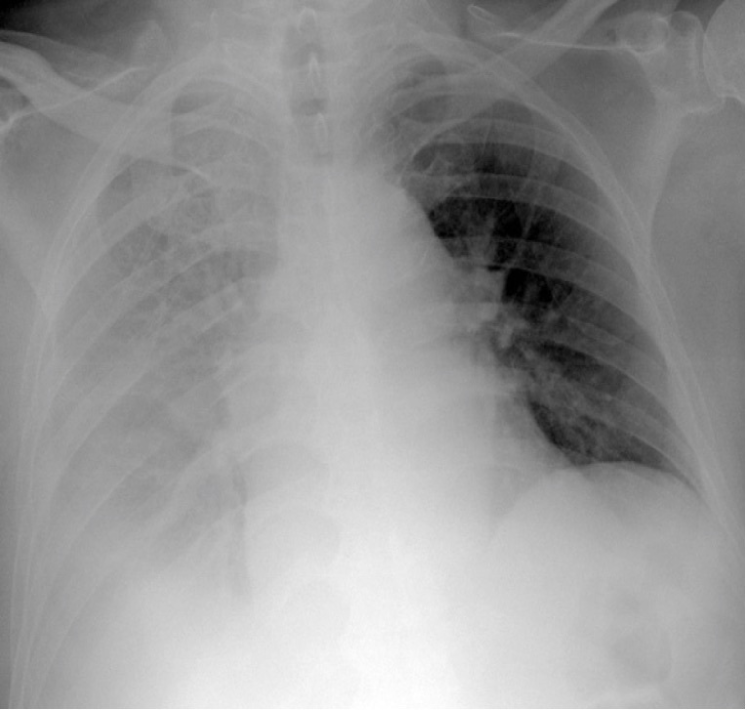

Refer to caption

(a) P-A

(b) Decubit

Figure 4: Pleural effusion in different projections: A bipedestation projection (a) shows the meniscus sign in which the fluid accumulates in the subpulmonary region, ascends through the thoracic wall and through the paramedian zone. In decubit projection (b) there is no meniscus sign. As the liquid goes to the most declining area there is a diffuse increase in hemithorax density and a loss of the net limit of the diaphragm with occupation of the pulmonary vertex by apical cap, costo-phrenic angle blunting and a thickening of the smaller fissure.

The projection information is highly relevant for diagnosis. For example, AP views, which are commonly used in pediatric patients, show an enlarged heart silhouette (Fig. 2(j)) that should not be interpreted as cardiomegaly, but merely the expected large-depth ratio of reversed organ observation (Fig. 3). Another illustrative example is the distinct pattern that pleural effusions have in the standing position (Fig. 4(a)), in which a typical meniscus sign is commonly found as opposed to decubit projections (Fig. 4(b)). Given that the number of different projections is unbalanced (for instance, PA followed by lateral projections typically comprise the majority of chest x-rays), there is the risk that none of the other projections will have sufficient instances with which to train models capable of discriminating pathological from non-pathological patterns in the context of the projection.